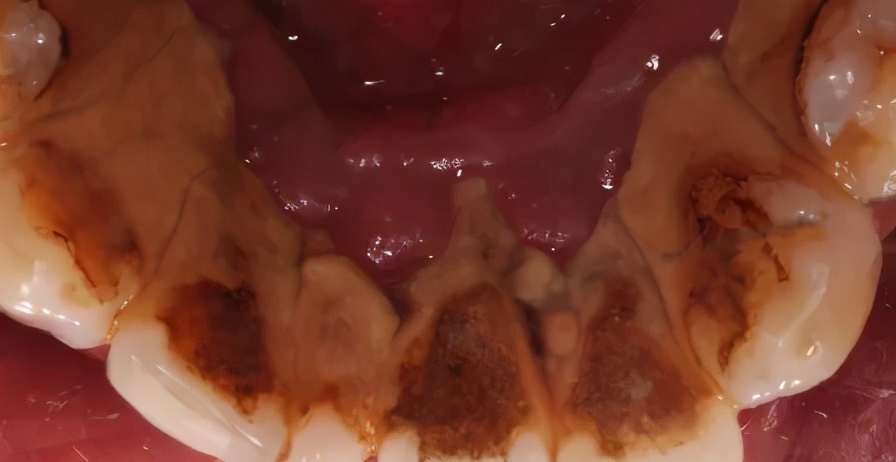

你见过这么厚的牙结石吗?

下图牙表面黄色的,就是 牙结石

如果牙结石多,平时刷牙就会出血,而且刷牙是清除软垢和菌斑,洗牙是清除牙结石。 牙结石比软垢和菌斑更坚硬,所以洗牙时出血是正常的 。洗牙之后等牙龈恢复健康就好啦。牙结石如果不及时去除,时间长了牙周炎就会找上门,最后只有一个结果——牙齿脱落。